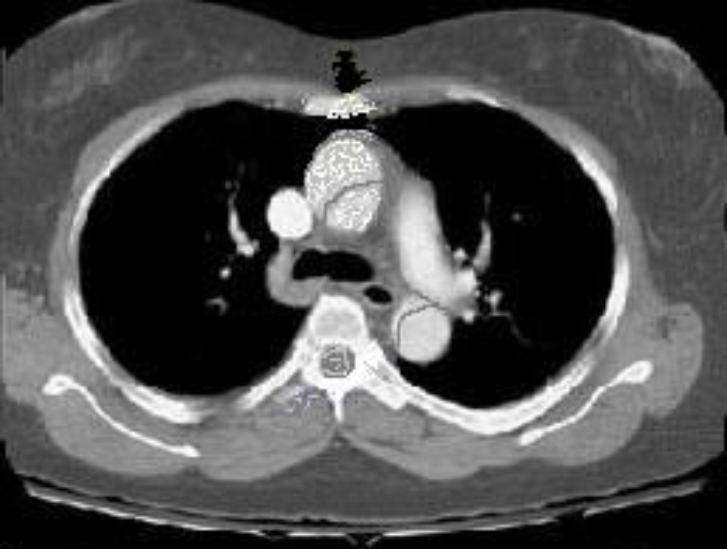

What type of dissection is shown here?

Type A aortic dissection as this is affecting the ascending aorta. The false lumen is clearly visible.

(Most common classification used is the Stanford classification –> split into A(ascending) and B(descending aorta involved)